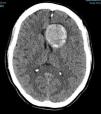

Más datosA 49-year-old woman suffered a first seizure episode. The brain CT scan (Fig. 1) revealed a giant aneurysm of the left internal carotid artery (ICA) with subtotal thrombosis (no CT-angio contrast uptake). Arteriography was decided (Fig. 2), showing a large left carotid-ophthalmic aneurysm, with a minimum patent portion (8 × 5 mm). The rest proved thrombotic. During arteriography, the patient developed hemiparesis and deviation of the vocal commissure, with arteriographic vasospasm that subsided with verapamil. Magnetic resonance imaging (Fig. 3) described the aneurysm with a left frontal parasellar location, measuring 4.2 × 3.9 × 3.6 cm, originating at the top of the left ICA and exerting a mass effect upon both anterior cerebral arteries and the left middle cerebral artery, as well as compression and right displacement of both frontal horns. The MR-angio study evidenced a 9-mm saccular dilatation in the supraclinoid portion of the left ICA, located within the lower third of the described lesion. A differential diagnosis with contained rupture of the aneurysm was considered. Surgery with clipping of the aneurysm was decided, with confirmation of its partial thrombosis and an intact capsule. The patient subsequently remained symptoms-free, with salt-wasting syndrome as the only posterior complication.